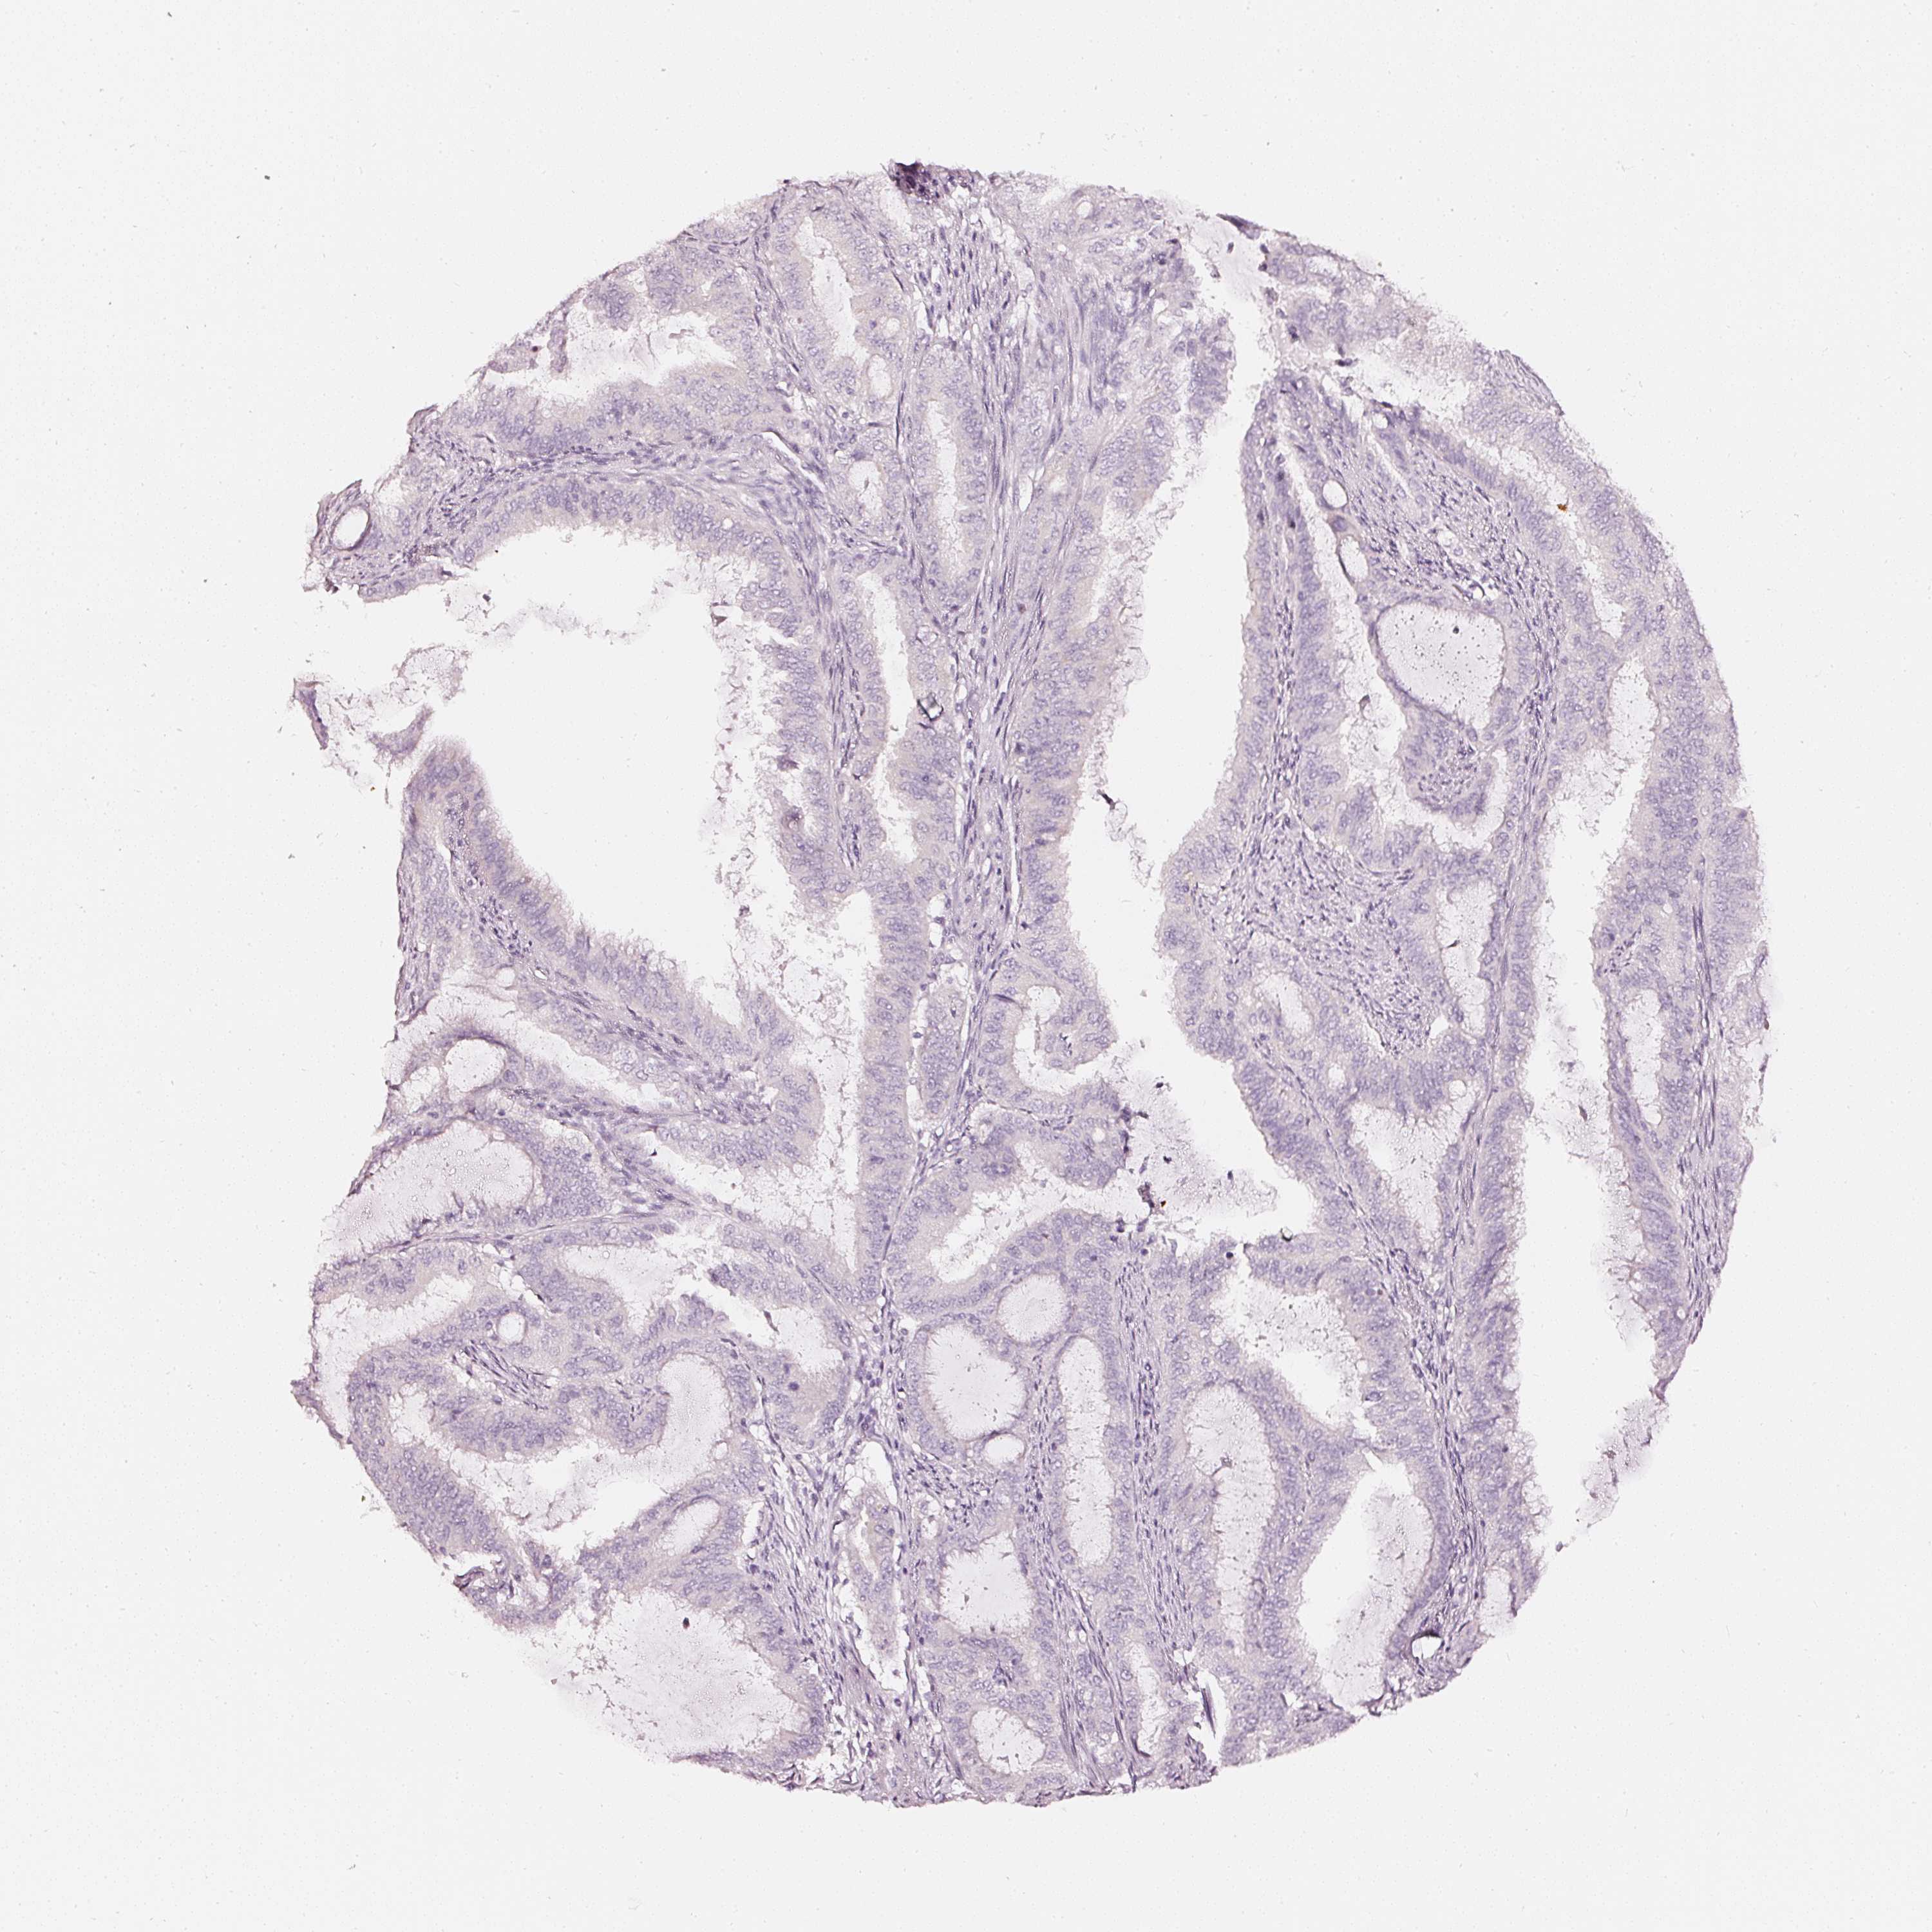

ENDOMETRIAL CANCER - Protein expressioni

A mouse-over function shows sample information and annotation data. Click on an image to view it in a full screen mode. Samples can be filtered based on level of antibody staining by selecting one or several of the following categories: high, medium, low and not detected. The assay and annotation is described here.

Note that samples used for immunohistochemistry by the Human Protein Atlas do not correspond to samples in the TCGA dataset.

Antibody stainingi

Antibody staining in the annotated cell types in the current human tissue is reported as not detected, low, medium, or high, based on conventional immunohistochemistry profiling in selected tissues. This score is based on the combination of the staining intensity and fraction of stained cells.

Each image is clickable and will lead to virtual microscopy that enables deeper exploration of all samples and also displays staining intensity scores, fraction scores and subcellular localization as well as patient and tissue information for each sample.

Adenocarcinoma, NOS

Adenoma, NOS

Adenocarcinoma, metastatic, NOS

Neoplasm, malignant, NOS